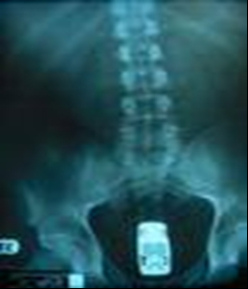

una diferente pero no se que motorizacion tenia ese vehiculo...

- 8b5e82afca.jpg (47.93 KiB) Visto 1457 veces